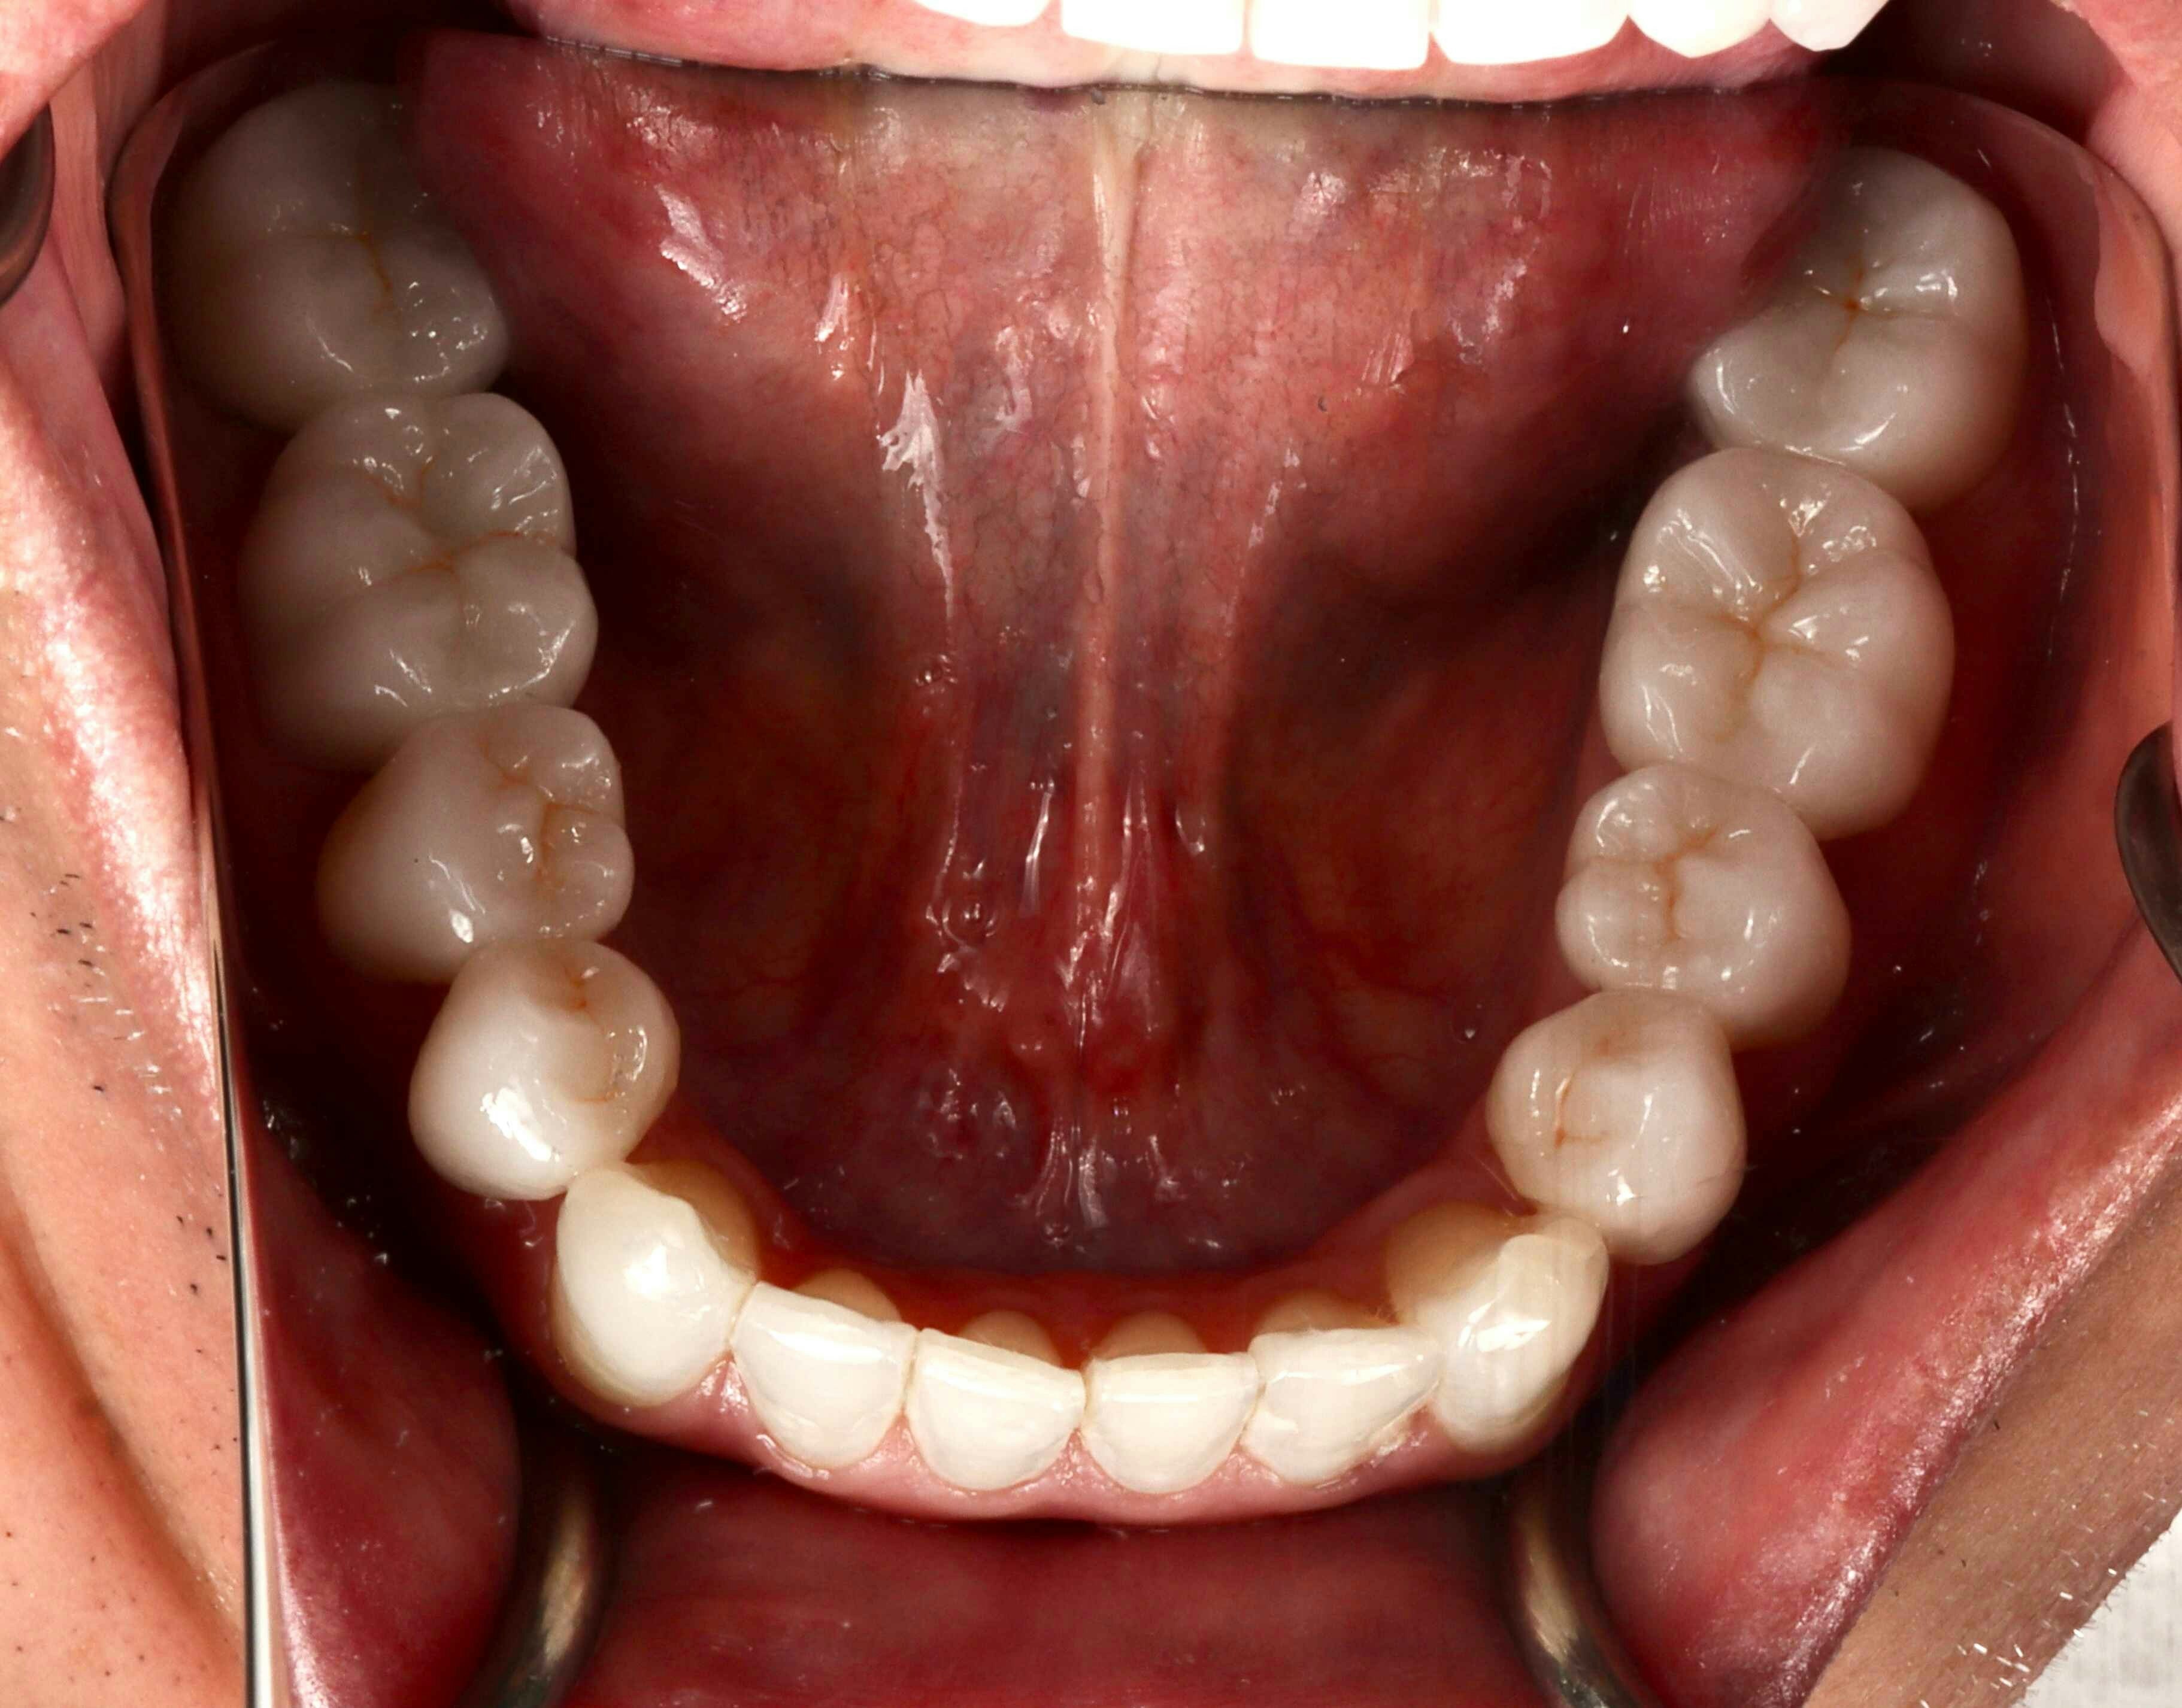

One of the main issues Harsha was dealing with was his habit of clenching and grinding his teeth. On top of that, many of his lower crowns were made flat, without the natural grooves and anatomy that teeth should have. These grooves and valleys are there for a reason, and when they're not properly included in dental work, it can lead to problems down the road.

Once the Invisalign treatment was complete, we replaced Harsha's lower crowns with new ones that had the proper anatomical features. This was a crucial step in ensuring that his bite would function correctly and comfortably.